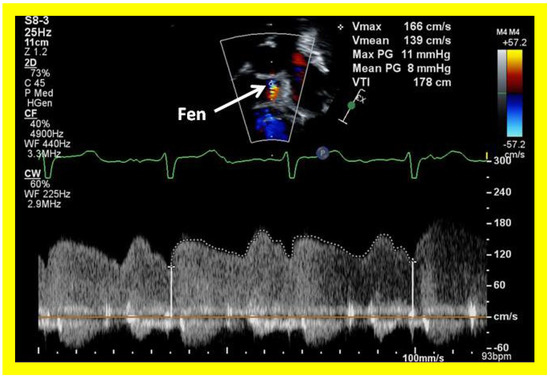

Surgically created fenestrations (Figure 50, Figure 51, Figure 52 and Figure 53) can also be demonstrated by color Doppler studies and the mean gradient across the fenestration (Figure 52 and Figure 53) is helpful in determining the physiologic state; a mean gradient of 4 to 8 mmHg is considered adequate.

Applsci 11 09472 g042

Figure 43. Selected video frames from apical views in two dimensional (A) and color flow imaging (B) modes demonstrating the right ventricle (RV) forming a cul-de-sac connection via a ventricular septal defect (VSD) with the left ventricle (LV). ATV, atretic tricuspid tricuspid valve, C, conduit, LA, left atrium.